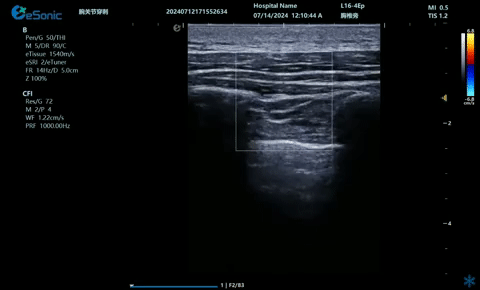

04

超声引导下神经根阻滞,也可以

做腰神经后支